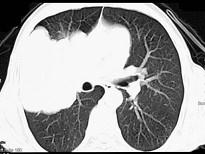

问题 50岁,男性,右侧胸痛、咳嗽、咯血3个月,请结合图像选择最可能的诊断 ( )

选项 A.纵隔肿瘤 B.肺结核 C.肺癌 D.胸膜间皮瘤 E.韦格肉芽肿

答案 C